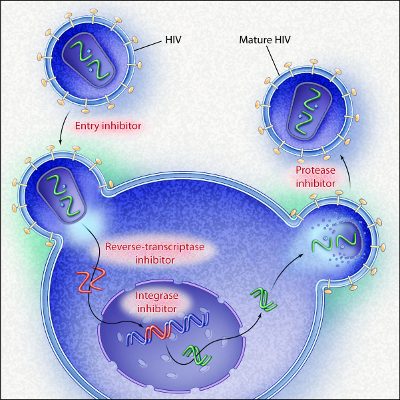

1981年12月10日

一组关于同性恋男性的病例报告成为了最早描述HIV病程的报告,故而算是里程碑性的。它报道了4个既往健康的同性恋男性受卡氏肺孢子虫感染、广泛粘膜念珠菌感染和多种病毒感染。4人中的3名长期未明原因发热,所有病人均对病原无抵抗力且淋巴结肿大。

1997年9月11日

Gulick的研究发现使用茚地那韦、齐多夫定和拉米夫定3种不同机制药物的联合,可以显著并持续抑制HIV的复制。这就是革命性的艾滋病鸡尾酒疗法的诞生。